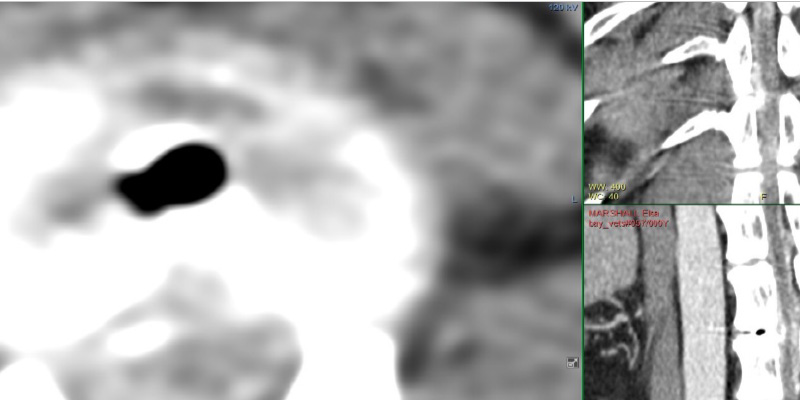

The following day, as Elsa’s clinical signs progressed, it was then appropriate to proceed with advanced imaging. One of our referral vets examined her again, identified grade II ambulatory paraparesis and slow pedal reflexes. A CT scan showed mild extradural cord compression at T12-13 (Figure 2) as well as multiple degenerative discs but none of these lesions causing cord compression.

Figure 2 Left: Axial view; the dark space depicts air which should not be there. This is a sign the disc extrusion has happened recently. Upper Right: The spinal cord (central, grey) is being compressed by disc contents (lighter colour). Lower RIght: sagittal view of air.